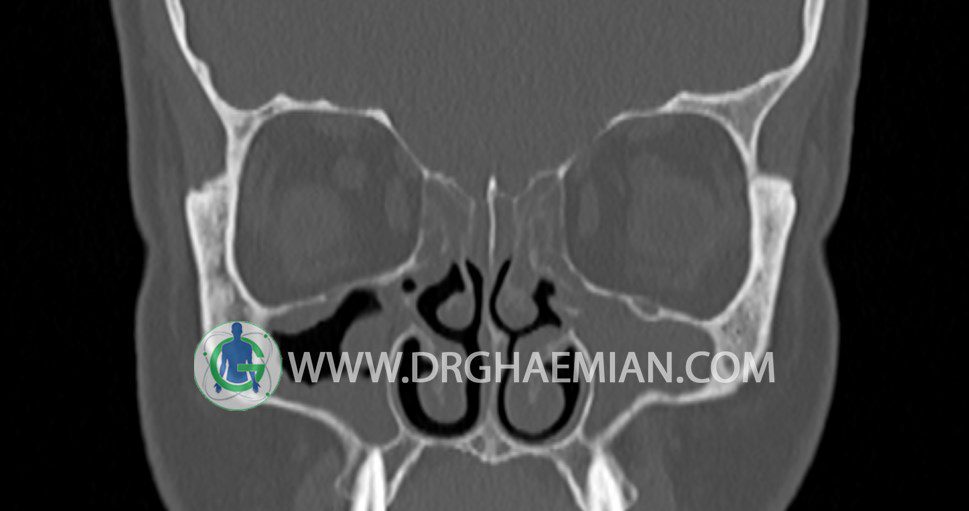

سی تی اسکن سینوس ها یک روش تصویربرداری است که با استفاده از تشعات ایکس تصاویری با جزییات از ناحیه خالی داخل صورت (سینوس ها) ایجاد میکند. در این کیس پانسینوزیت، افزایش ضخامت مخاط و انسداد omc و انحراف سپتوم دیده می شود.

در HRCT اسپيرال از سينوس هاي پارانازال مقاطع کرونال و آگزيال ( 16 اسلايس و مقاطع ظريف 1.5 mm بدون فاصله ، با پنجره استخواني و نسج نرم ) :

شواهدی از توده، سطح گاز – مايع، کدورت سينوسها و اروژن ديواره سينوسها ديده نمی شود.

کونکا بولوزا در کونکای ميانی دوطرف ديده نمی شود.

– افزايش ضخامت مخاطي در سينوس هاي اتموئيد ، اسفنوئيد و ماگزيلاري دو طرف و

با شدت کمتر در فرونتال نشانه pansinusitis همراه با انسداد omc دو طرف و انحراف

سپتوم مياني بيني به راست و چپ مشهود است.